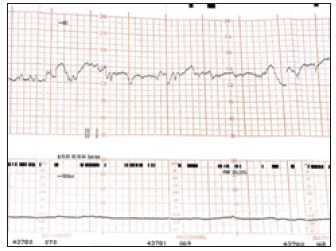

Figure 2:NST performed on 06/17/16.

Figure 3:NST performed on 07/17/16.

The patient was immune to rubella, toxoplasma gondii and cytomegalovirus. The patient was enrolled in our fetal surveillance program which included weekly fetal heart rate monitoring (Non- Stress Test, NST) as part of a biophysical profile and fetal biometric measurements every three weeks. The weekly non-Stress tests performed were all reactive. On Figure 1 & 2 we can appreciate two reactive tracings at two different dates. Moderate variability, with adequate baseline fetal heart rate and accelerations are seen in both fetal heart rate tracings. No decelerations were noted [3]. In this case we note that in spite of the Zika’s viral effect on the fetus, there was no evidence of central nervous system depression as evidenced by the fetal heart rate tracing and the Apgar scores at birth were 9 and 9 at 1 and 5 minutes. Serology testing on the newborn later confirmed Zika virus infection with a positive Zika IgM antibody.

In the case presented, microcephaly and dilated lateral ventricles diagnosed by ultrasound imaging, and the positive maternal flavivirus serology led to the presumptive diagnosis of perinatal Zika. The viral infection which was confirmed by culture at birth. It is remarkable that the intracranial lesions in this case seem to spare the fetal central nervous system control over the cardiovascular system as we know it. Precisely the fetal cardiac activity is under the dual influence of the sympathetic and parasympathetic systems, causing a succession of relative tachycardia alternating with bradycardia tendencies, thus the baseline variability which we associate with adequate fetal oxygenation (Figure 2 & 3). Antepartum surveillance is widely used to identify fetal compromise especially those instances associated with acid base disturbances due to oxygen deprivation [4-6]. This often allows obstetricians to intervene before further compromise or even fetal death occurs.

The biophysical profile which evaluate five parameters related to the fetal wellbeing status namely the fetal body movements, tone, respiratory movements the amniotic fluid volume and the fetal cardiac activity assessed by the non-stress test (NST), often likened to an intrauterine equivalent of the Apgar’s score. In this patient, the weekly biophysical profile was reassuring, including a reactive NST (Figure 2 & 3) at every session until the day of delivery when the immediate neonatal evaluation yielded an Apgar score of 8 at 1 minute and 9 at 5 minutes [7]. The Zika virus is one of the most recently known infectious teratogens, responsible for multiple intracranial anomalies and loss of cerebral tissue, associated with fetal microcephaly. Our experience in monitoring the wellbeing of this fetus severely affected by the maternal Zika virus infection serves to show that at least in some fetuses so affected our monitoring tools can reliably predict the fetal status and guide our decision on the timing of delivery and avoid worsening of the neonatal prognosis for an already compromised intrauterine patient.